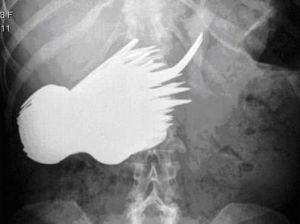

異食癖患者吃掉78件餐具後的胸部CT驅蟲